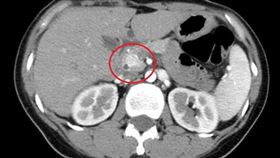

語無倫次亂打人記不得 元凶竟是「腫瘤」

47歲的黃姓婦人,兩年前開始出現語無倫次及在地上翻滾...

2023/11/26 14:09